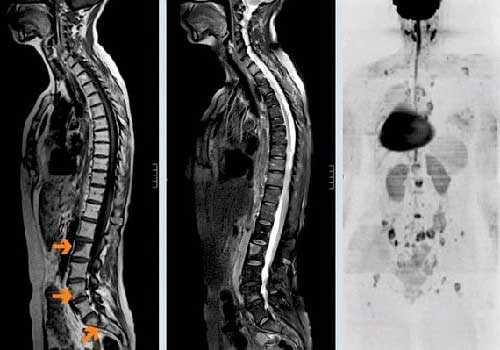

Патологические переломы возникают при разрушении более 50% кортикального слоя. Чаще всего выявляются в позвонках, второе место по распространенности занимают переломы бедренной кости, обычно – в области шейки или диафиза. Отличительной особенностью патологических переломов позвоночника при метастазах в кости является множественность поражения (одновременно выявляется нарушение целостности нескольких позвонков). Как правило, страдает грудной или поясничный отдел. Повреждения могут сопровождаться компрессией нервных корешков или спинного мозга.

Компрессия спинного мозга

Компрессия спинного мозга выявляется у 1-5% пациентов с метастатическими поражениями позвоночника. В 70% случаев причиной нарушений становятся метастазы в грудные позвонки, в 20% - в поясничные и крестцовые позвонки, в 10% случаев – в шейные позвонки. При метастазах в кости могут выявляться как острые (при сдавлении костным фрагментом), так и постепенно прогрессирующие (при сдавлении растущей опухолью) расстройства. При сдавлении растущим новообразованием пациентов с метастазами в кости беспокоят нарастающие боли. Развивается мышечная слабость, выявляются нарушения чувствительности. На заключительной стадии возникают парезы, параличи и нарушения функции тазовых органов.

При сдавлении фрагментом кости клиническая картина компрессии спинного мозга развивается внезапно. На начальных стадиях оба вида компрессии обратимы (полностью или частично). При отсутствии своевременной медицинской помощи в течение нескольких часов или дней паралич становится необратимым. Своевременное адекватное лечение позволяет уменьшить выраженность симптомов, однако восстановление способности к самостоятельному передвижению отмечается всего у 10% больных с уже развившимся параличом.

Диагноз устанавливается на основании анамнеза (данных о наличии первичного злокачественного новообразования), клинической картины и результатов дополнительных исследований. Отсутствие информации об уже диагностированном онкологическом заболевании не является основанием для исключения метастазов в кости, поскольку первичная опухоль может протекать бессимптомно. При наличии неврологических нарушений проводят неврологический осмотр. На начальном этапе обследования выполняют сцинтиграфию. Затем больных направляют на рентгенографию, КТ или МРТ кости для уточнения характера и распространенности поражения. Для выявления гиперкальциемии назначают биохимический анализ крови.

О наличии онкологического заболевания свидетельствует положительный анализ крови на онкомаркеры. На начальном этапе диагностики больным с подозрением на метастазы в позвоночник назначают рентгенографию позвоночника. На ранних стадиях метастазирования рентгенологические признаки поражения позвонков могут отсутствовать, поэтому при отрицательном результате исследования пациентов с подозрением на метастазы в позвоночник направляют на сцинтиграфию, КТ и МРТ позвоночника. Для выявления первичной неоплазии и вторичных очагов проводят УЗИ органов брюшной полости, рентгенографию органов грудной клетки, маммографию и другие диагностические процедуры. Дифференциальную диагностику метастазов в позвоночник осуществляют с сосудистыми поражениями, последствиями воспалительных заболеваний, вторичной демиелинизацией и первичными неоплазиями позвоночного столба.